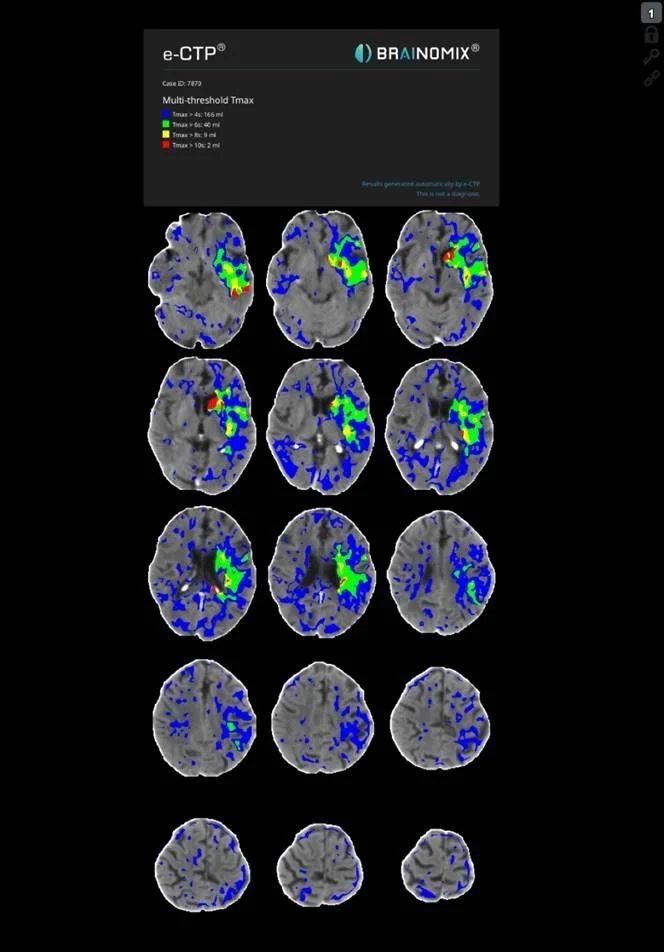

Stroke CT workup showed 16 ml well delignated infarct of the head of caudatenucleus and putamen (ASPECTS 8), a proximal left M1 occlusion and 40 ml of perfusion lesion in the MCA territory (18:25, Brainomix). No thrombolysis.